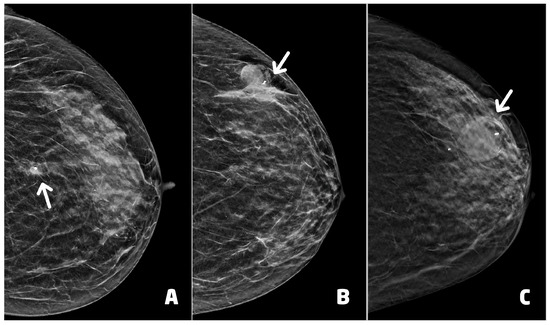

Thirty (30) BC presented as microcalcifications with (four) or without (26) architectural distortion. Six (6) BC presented as architectural distortion without microcalcifications, and one BC presented as an inhomogeneous area of asymmetrical density with scattered microcalcifications (Figure 4). Of the 37 BC diagnosed, 26 were in stage 0 and 11 in stage IA (Table 1).

Figure 4. Examples of suspicious non palpable lesions undergone VABB: (A) 66 year-old woman, 2D synthetic view of the left breast showing a cluster of microcalcifications at the upper outer quadrant, in periareolar region (circle), ductal carcinoma in situ, G1; (B) 53 year-old woman, 2D-FFDM view of right breast showing a cluster of microcalcification in the equatorial region (circle), ductal carcinoma in situ, G3; (C) 55 year-old woman, 2D synthetic view of the left breast showing an area of architectural distortion at the union of the upper quadrants (circle), invasive ductal carcinoma, tubular variant.